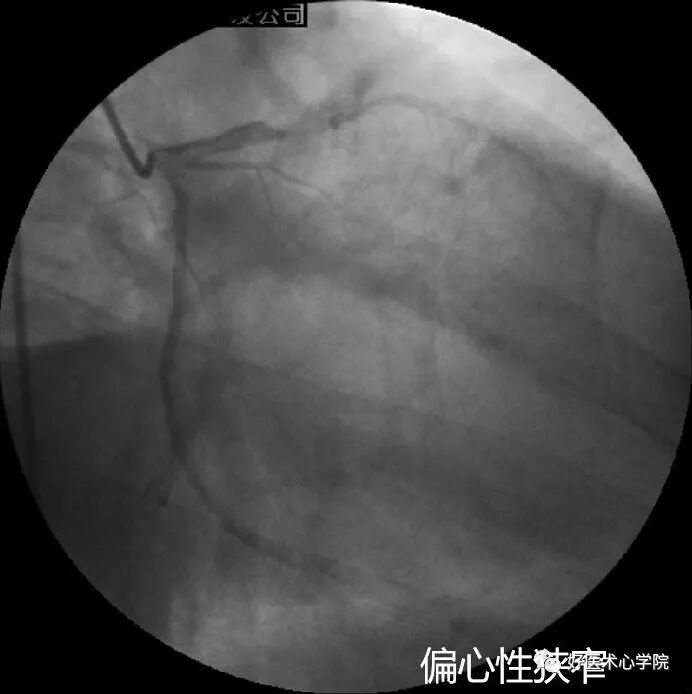

偏心性狭窄:

冠状动脉粥样斑块以管腔中心线为中心不均匀向中心缩窄,或在中心线一侧缩窄;不同投照角度狭窄程度不相同,合理选择投照角度、以最重狭窄为准,已证明的偏心病变IVUS中仅63%显示为偏心性斑块,IVUS和造影评价病变偏心性的一致性仅为53%

造影导丝是什么珍藏 冠脉造影从流程到诊断,基础必备!_https://www.jmylbn.com_新闻资讯_第80张